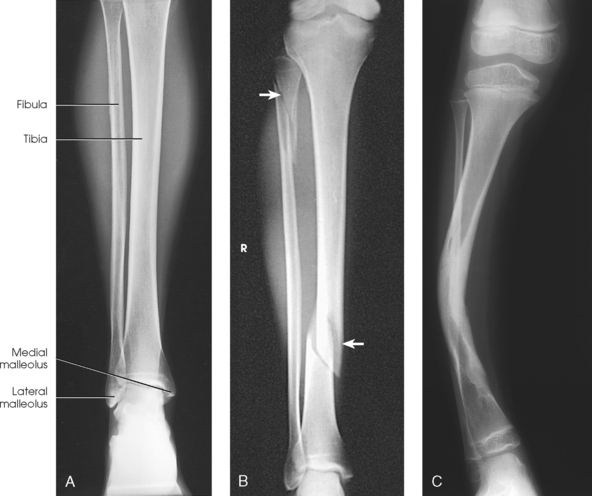

For this projection and the lateral and oblique projections described in the following sections, the long axis of the IR is placed parallel with the long axis of the leg and centered to the midshaft. Unless the leg is unusually long, the IR extends beyond the knee and ankle joints enough to prevent their being projected off the IR by the divergence of the x-ray beam. The IR must extend 1 to 1½ inches (2.5 to 3.8 cm) beyond the joints. When the leg is too long for these allowances, and the site of the lesion is unknown, two images should always be made. In these instances, the leg is imaged with the ankle joint, and a separate knee projection is performed. Diagonal use of a 14 × 17 inch (35 × 43 cm) IR is also an option if the leg is too long to fit lengthwise and if such use is permitted by the facility. The use of a 48-inch (122-cm) SID reduces the divergence of the x-ray beam, and more of the body part is included.